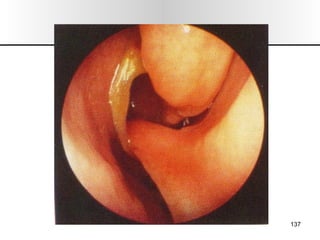

• 4.

EMBRIOLOGIA DE NARIZY SENOS PARANASALES 3 sem Prosencefalo = placodas olfatorias, separadas por tejido del proceso frontal 4 sem La periferia de las placodas olfatorias toman forma de herradura Su centro de hunde para formar los mamelones olfatorios Su crecimiento dorso caudal aproxima a la línea media, sobre el techo de la cavidad bucal. Los mamelones olfatorios % al proceso frontal 1.- pared medial 2.- pared lateral Parte medial crece mas rápido y forman 1.- columela 2.- proceso premaxilar